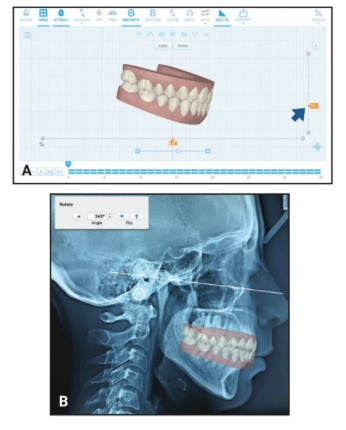

L’articolo descrive una tecnica che affronta una problematica specifica nella pianificazione ortodontica virtuale: l’orientamento del piano occlusale nei software di trattamento digitale.

La metodica proposta prevede:

- L’utilizzo di radiografie laterali del cranio orientate secondo il piano di Francoforte

- Fotografie frontali con retrattori guanciali

- Sovrapposizione del modello digitale alle immagini del paziente

Questa procedura consente di ottenere informazioni più precise riguardo ai requisiti di torque, all’arco del sorriso e alle inclinazioni assiali durante la pianificazione ortodontica.